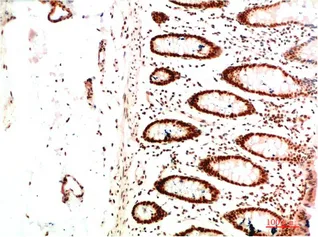

CDX2(14H6)Mouse Monoclonal Antibody

Cat: AMM08595

Size1:50μL Price1:$118

Size2:100μL Price2:$220

Size3:200μL Price3:$380

Application:WB,IF-P,IF-F,ICC/IF,IHC-P

Reactivity:Human,Mouse,Rat

Conjugate:Unconjugated

Optional conjugates: Biotin, FITC (free of charge). See other 26 conjugates.

Gene Name:CDX2